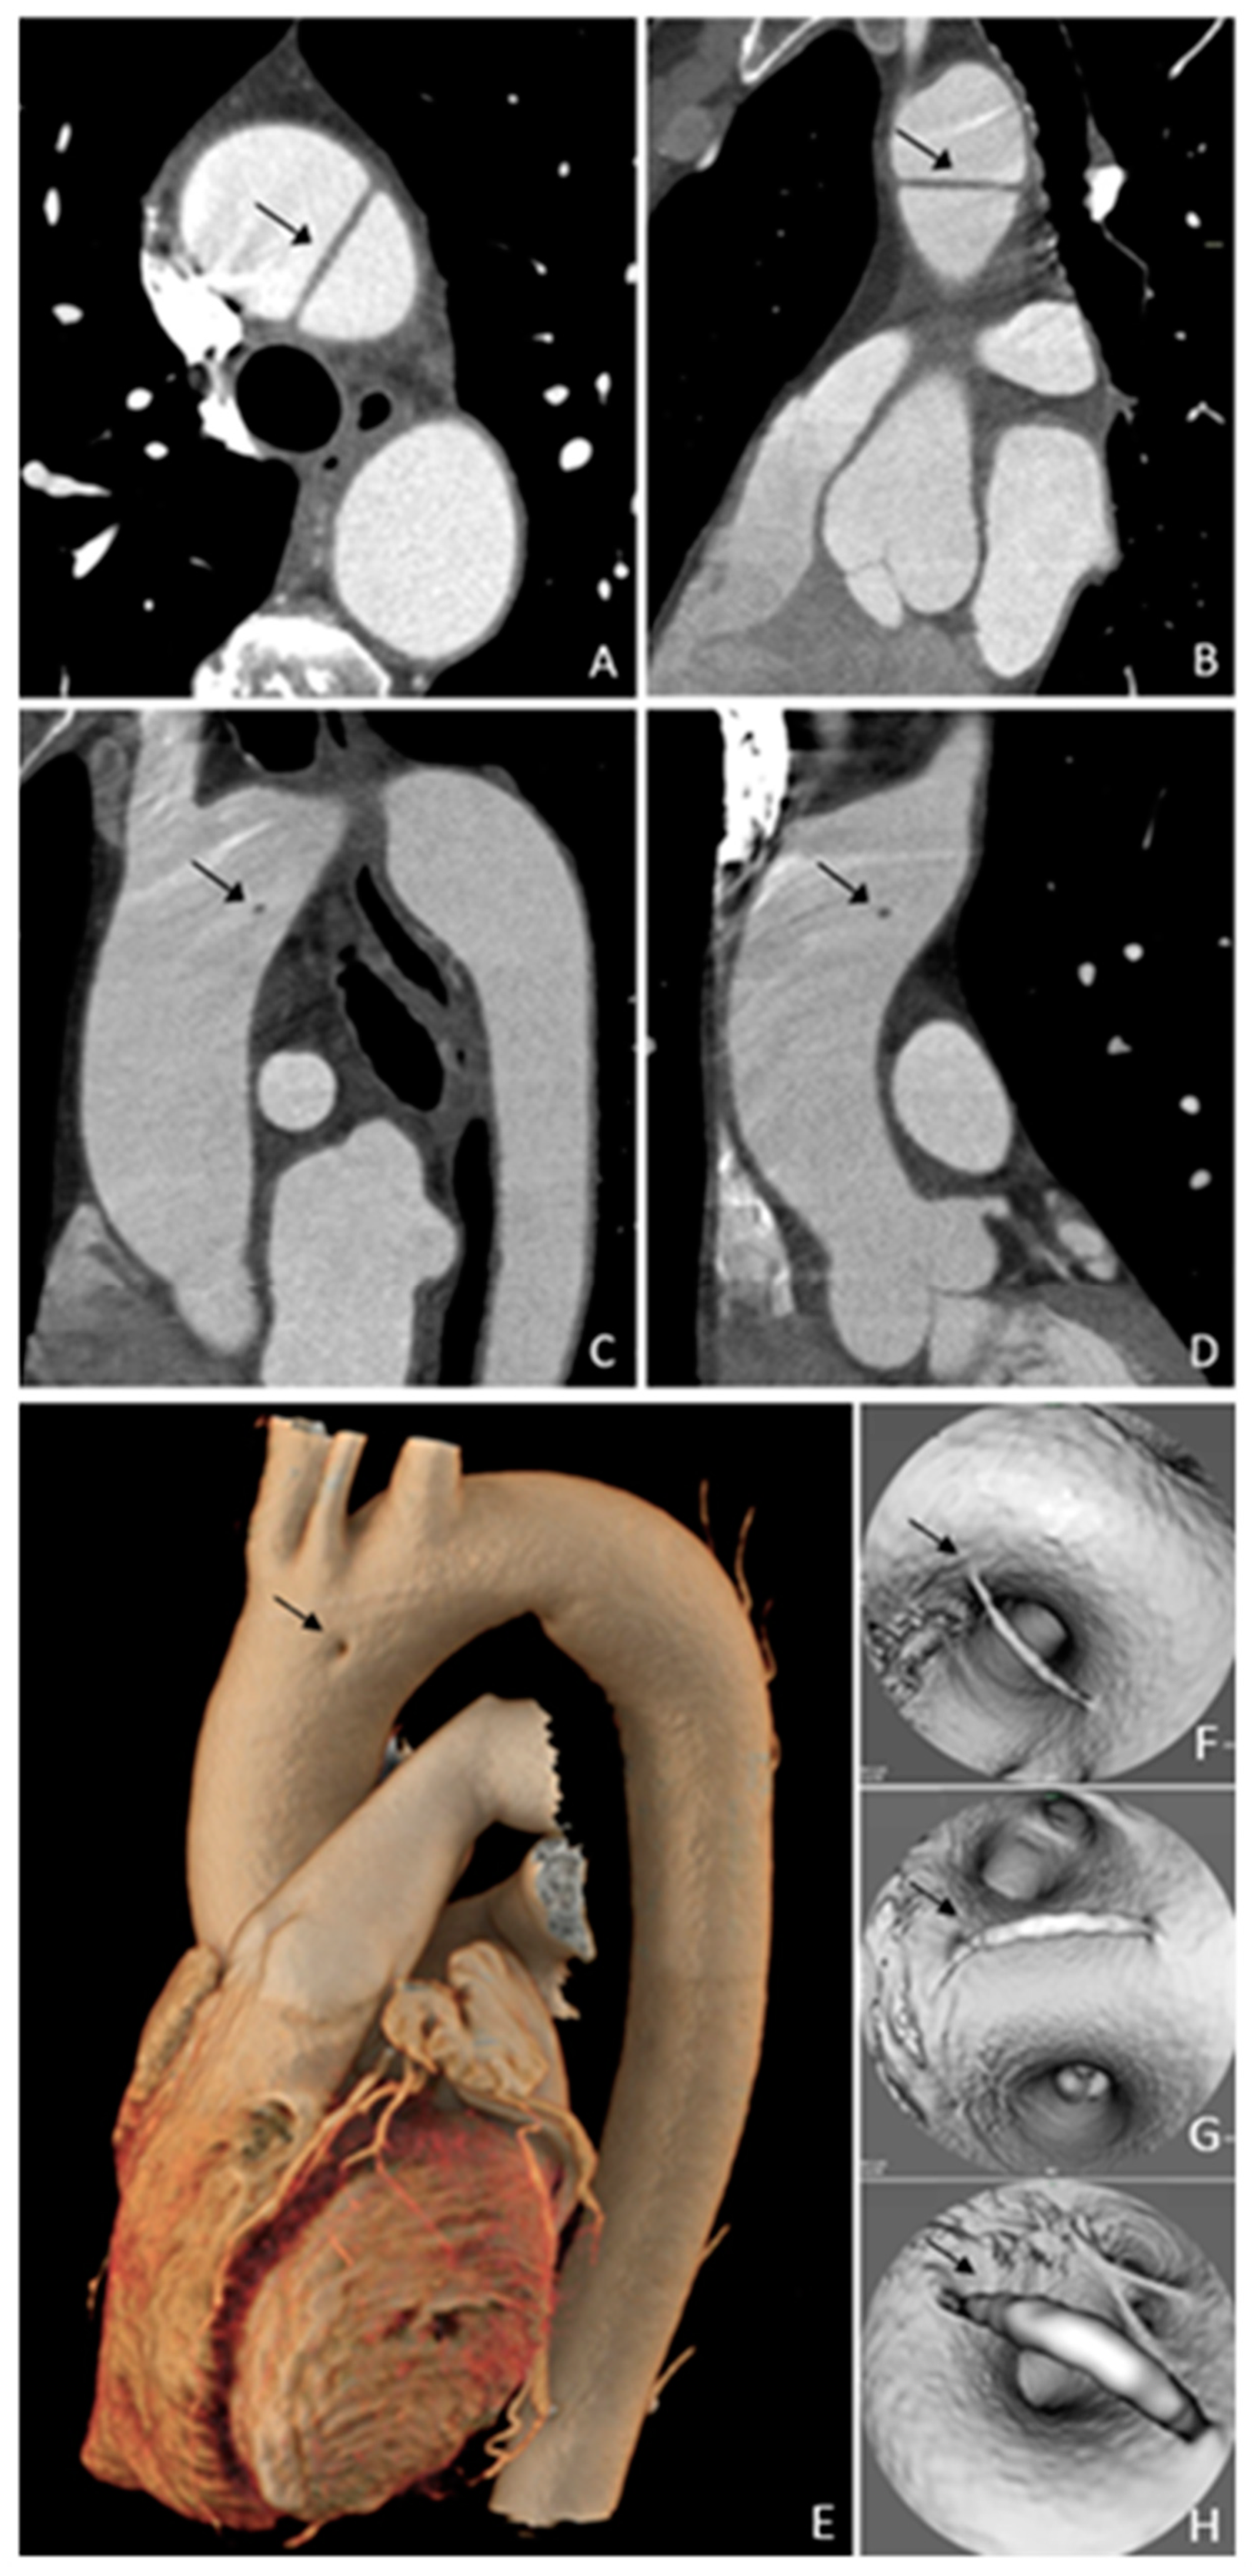

V Aortic Arch Remnant

Tagliati, C.; Fogante, M.; Lamja, S.; Cerimele, C.; Quaranta, A.; Matarrese, A.A.; Battista, D.; Bernardini, A.; Argalia, G.; Carbone, I.; et al. V Aortic Arch Remnant. Diagnostics 2025, 15, 1036. https://doi.org/10.3390/diagnostics15081036